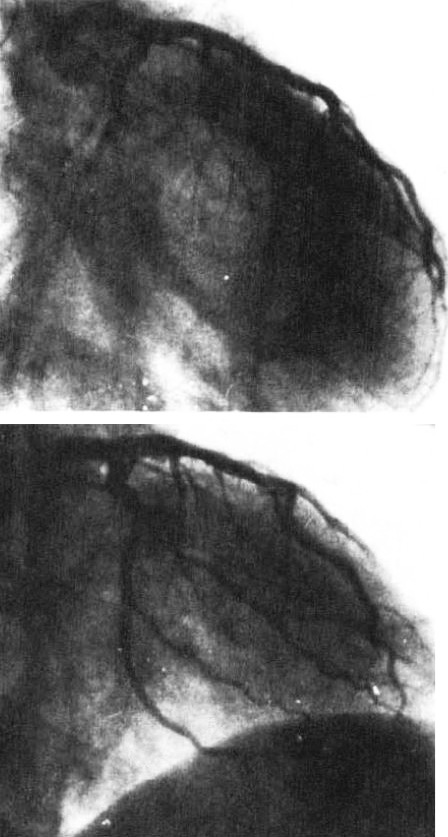

図6.急性心筋梗塞.(上)左冠動脈回旋枝の閉塞.(下)ストレプトキナーゼ冠動脈内投与後.回旋枝が良好に造影されている.

対象は5例の急性心筋梗塞例で, いずれも緊急入院後,まずニトログリセリンを冠動脈に投与し,直後よりストレプトキナーゼをまずボーラスで1~2万単位,その後15~60分かけて1,000~2,000単位/時で持続動注し,全例で開存,臨床症状の軽快ないし消失が得られた(図6).治療経過中に冠動脈造影を頻繁に繰り返して,再疎通の状態を確認している.